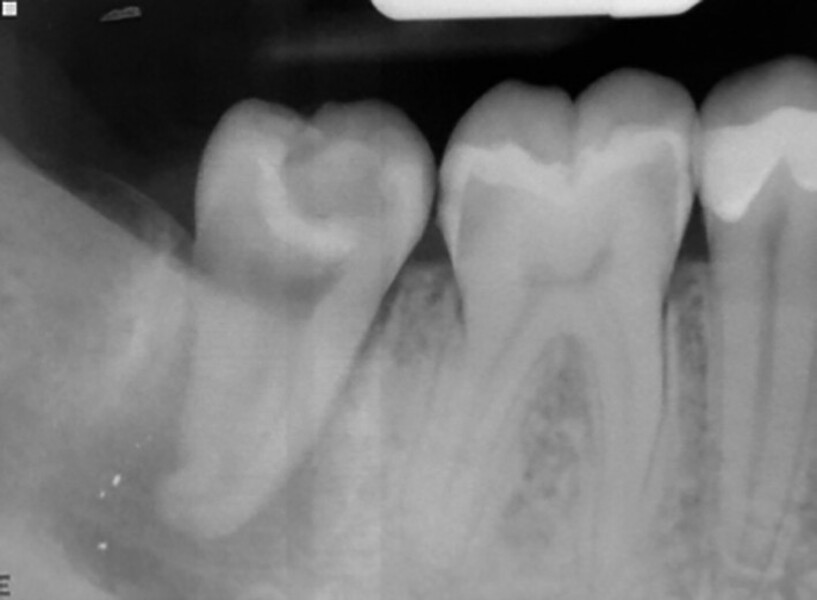

Fig. 14a: Clinical image: Pre-op.